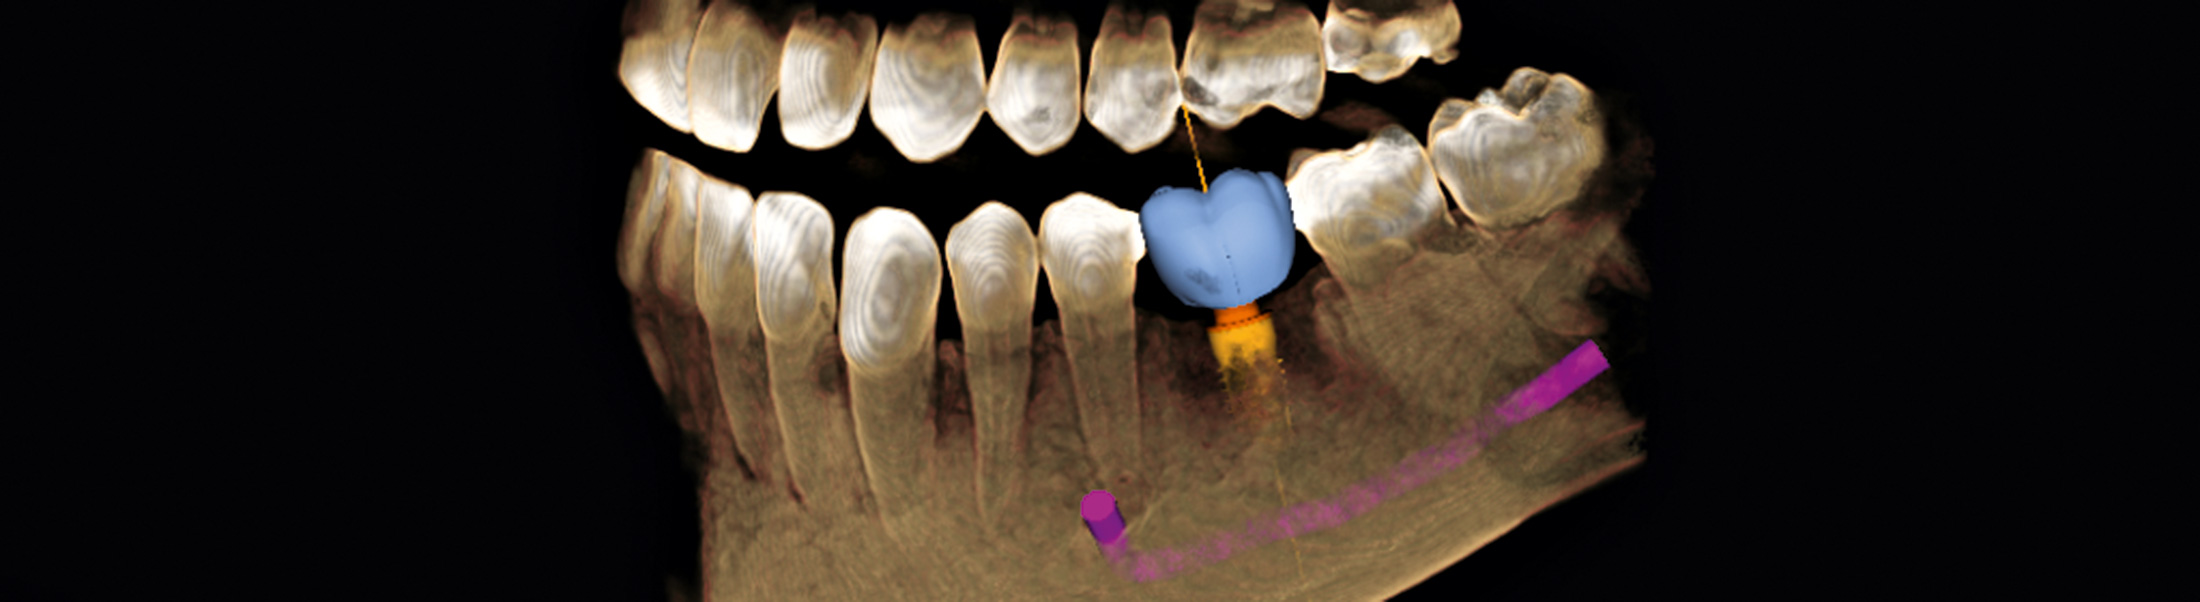

Unser Digitaler Volumentomograph SIRONA ORTHOPHOS SL 3D bietet mit der Möglichkeit der Darstellung von Hochkontraststrukturen eine breite Indikationsspalette. Durch die exzellente Kontrastierung von Hartgeweben und die hochauflösenden Bilder der digitalen Volumentomographie kann eine sichere Basis zur pröimplantologischen Diagnostik und virtuellen Planung der Implantatpositionierung erstellt werden. Die dreidimensionalen Bilder der digitalen Volumentomographie können die Sicherheit für den Patienten vor einem operativen Eingriff deutlich erhöhen.